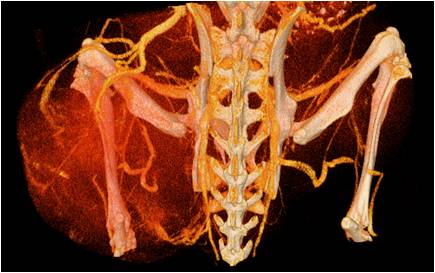

心血管

胸部和心血管的層析成像 胸部和心血管的3D圖像